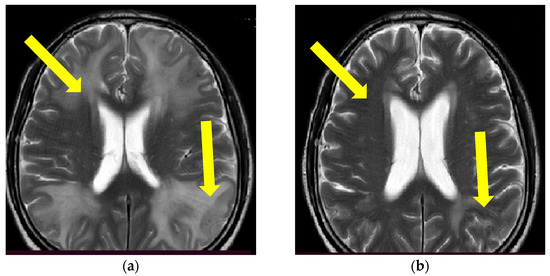

Figure 5.

MR axial T2*W sequence (a,b) showing multilocal punctiform signal hypointensities located diffusely in the subcortex and periventricular posterior region (lobar distribution). Yellow circles in (a) are showing multiple multifocal punctiform hypointensities dominantly right frontotemporally and occipitally, and in (b) bitemporal multifocal hypointensities (Patient No. 3).

Because of high clinical suspicion of probable CAA-rI, the treatment with pulse methylprednisolone therapy (1 g/daily) for 5 days was initiated, followed by oral prednisone (1 mg/kg) and azathioprine introduction (50 mg/day, as a corticosteroid sparing agent). The patient’s condition significantly improved, and his control brain MR evaluation showed partial regression in the initial findings. However, the patient developed an acquired intrahospital gastrointestinal infection with Clostridium difficile five days after starting azathioprine therapy and his somatic state, further complicated with respiratory insufficiency, and had to be intubated and connected to mechanical ventilation for a period of 10 days in the intensive care unit. Meanwhile, the doses of both immunosuppressive treatments were significantly reduced. Thus, the patient developed an epileptic seizure manifesting as myoclonus in the region of the left face and left arm, which rapidly progressed into a series of focal epileptic seizures despite antiepileptic treatment introduction (levetiracetam 3 × 1000 mg, midazolam 30 mg IV). A standard electroencephalogram evaluation showed periodic lateralized epileptiform discharges over the right central parietal region (one per second) and were consistent with epilepsia partialis continua. Control MR imaging showed stationary findings where a partial regression of initial WMH lesions was described. Unfortunately, the patient’s somatic state declined further due to systemic infection leading to respiratory insufficiency followed by cardiac arrest in the next 24 h, which resulted in a lethal outcome.